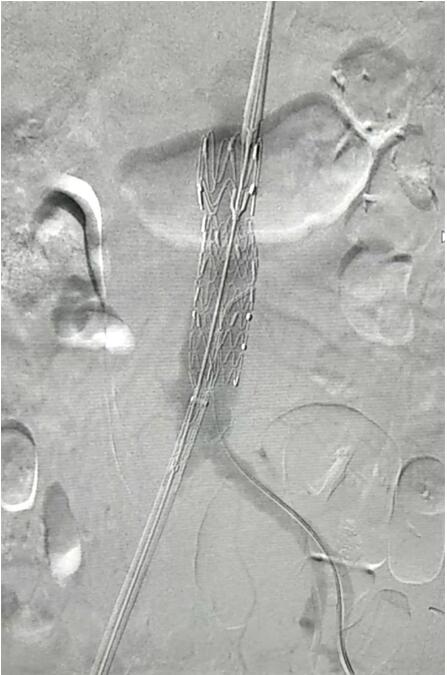

血管介入科行腹主動脈瘤覆膜支架隔絕術(shù)(“褲衩”支架植入)。圖1